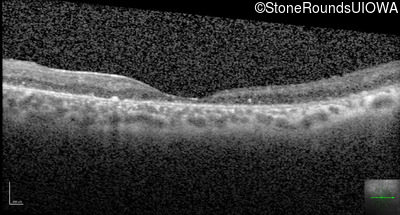

Optical Coherence Tomography - Left - 10/100 -2

Exemplar / OCT Stack